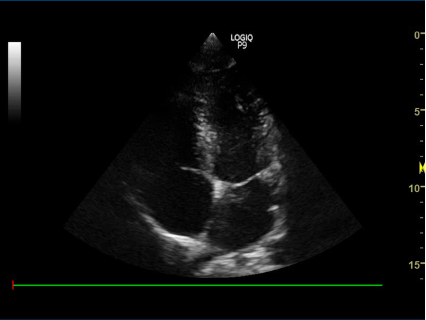

1) Subcostalt 4-kammer billede:

- Nævn strukturerne:

proben skal pege mod patientens ve. side